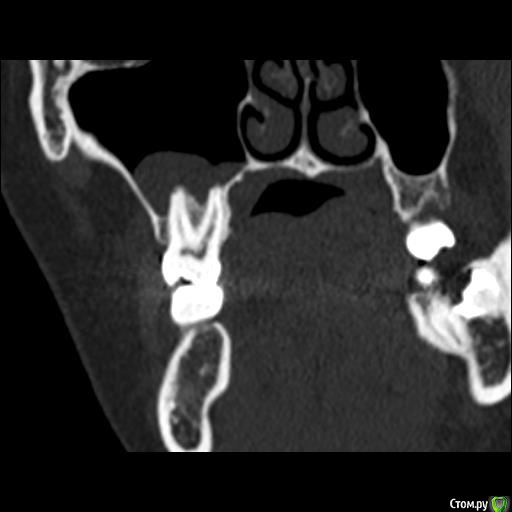

Юлия2386 Опубликовано 30 июля, 2020 Поделиться Опубликовано 30 июля, 2020 Добрый день, уважаемые врачи! Прошу вашей помощи, так как уже замучалась я конкретно. У меня уже 9 месяцев боли в правой стороне лица давящего характера. Давит на лоб, глаз, иногда висок. С декабря 2019 выявили фронтит-гайморит, проходила лечение у Лора и ещё невролога. Окончательного результата по выздоровлению за это время не достигнуто. Видимо это одномерный гайморит, так как постоянно какое-то воспаление формировалось у зубов 1.6;1.7;1.8. Многие стоматологи не видят проблем в зубе 1.6. Посоветовали удалить зуб 1.8 так как там был глубокий десневого карман. Удалила, а воспаление разрослось ещё больше (после удаления поцарапала щеку зубом 1.7, возможно из-за этого разрослось воспаление?!) После удаления прошёл месяц, а картина сейчас такая https://yadi.sk/d/ziceEN_jVZ9IkwВ итоге последний врач сказал, что все-таки проблема идёт от зуба 1.6, так как не запломбирован один канал, но из-за того что у зуба входят корни в гайморовых пазуху, лечить его не видет смысла, порекомендовал его удалить и через лунку вычиститься всю слизь, но он этим не занимается. Теперь я замешательстве и не знаю, что мне с этим делать, а самое ужасное, что глаз от этого болит( Уважаемые доктора, очень прошу вашей помощи, выскажите пожалуйста ваше мнение и может посоветуете к кому с этим можно обратиться в Москве. Ссылка на комментарий

wladdX Опубликовано 31 июля, 2020 Поделиться Опубликовано 31 июля, 2020 Представленная спиральная КТ не позволяет детально рассмотреть корневые каналы зубов и тп, чтобы получить какое-то внятное суждение.На уровне зубов 18, 17 и 16 есть локальное утолщение слизистой оболочки синуса и это всё, что из этого исследования можно выяснить. Адекватность обтурации корневых каналов зуба 16 оценить не представляется возможным (по крайней мере в моём понимании).Я бы порекомендовал сделать КЛКТ (конусно-лучевую компьютерную томографию), используемую в стоматологии. Ссылка на комментарий